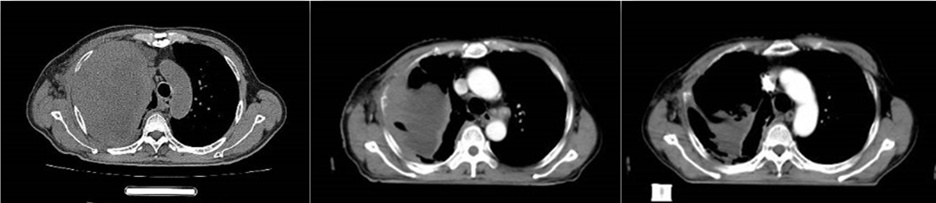

治疗过程中,放疗二科及放疗室团队始终密切关注患者病情变化,借助锥形束计算机断层扫描技术(CBCT)对肿瘤情况进行及时监测,纠正因体位变动带来的位置偏差,确保放疗精准“命中”肿瘤。仅经过8次放疗后,患者的病情便出现了显著改善,原本占据整个右侧胸腔的肿瘤明显缩退,喘憋症状大幅缓解,咳嗽、咳痰症状也基本消失。团队又及时为患者进行再次定位,结合最新影像学检查结果调整靶区与晶格剂量分布,实施更精准的后续放疗。患者病情得以良好控制后,科室再次提请院级MDT讨论,在多学科专家的讨论下为患者制定了进一步药物治疗方案。

影像图依次为:患者治疗前、第8次放疗后、第17次放疗后。